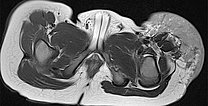

Axial slice of MRI (T2-weighted, fat-saturated) also clearly shows the infiltration of the musculature by the mass. Hemangiomas as vascular tumors can also exhibit such infiltration without necessarily being malignant.

Axial T2-weighted MRI without fat saturation shows the tumor as homogeneous and only slightly hyperintense. It is more hyperintense than muscle, but overall much less hyperintense than the surrounding subcutaneous adipose tissue.